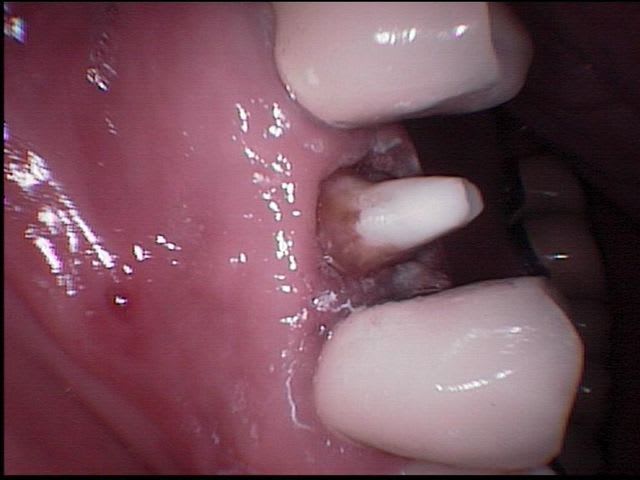

patient reçu un mardi soir en urgence, se plaint d'une voussure persistante et douleureuse en regard de la 15 couronnée en céramique depuis une dizaine d'année.

Le soir même je repère l'entrée de la fistule grâce à mes loupes, je fais sous anesthésie un débridement au laser diode sous eau oxygénée à 10 volumes.

Je donne un devis au patient et lui propose de traiter la dent en endo et en prothèse la semaine suivante, il accepte et le vendredi suivant, je le reçois afin d'executer le traitement prévu, il m'annonce que la voussure et la douleur avaient disparu spontanément le mercredi matin.